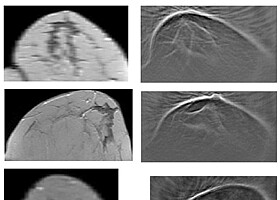

Heart models for the treatment of atrial fibrillation

Individual, digital heart models can be used to test therapies in order to select the one that promises the greatest success. A KIT method creates patient-specific virtual images of the heart from clinical data.